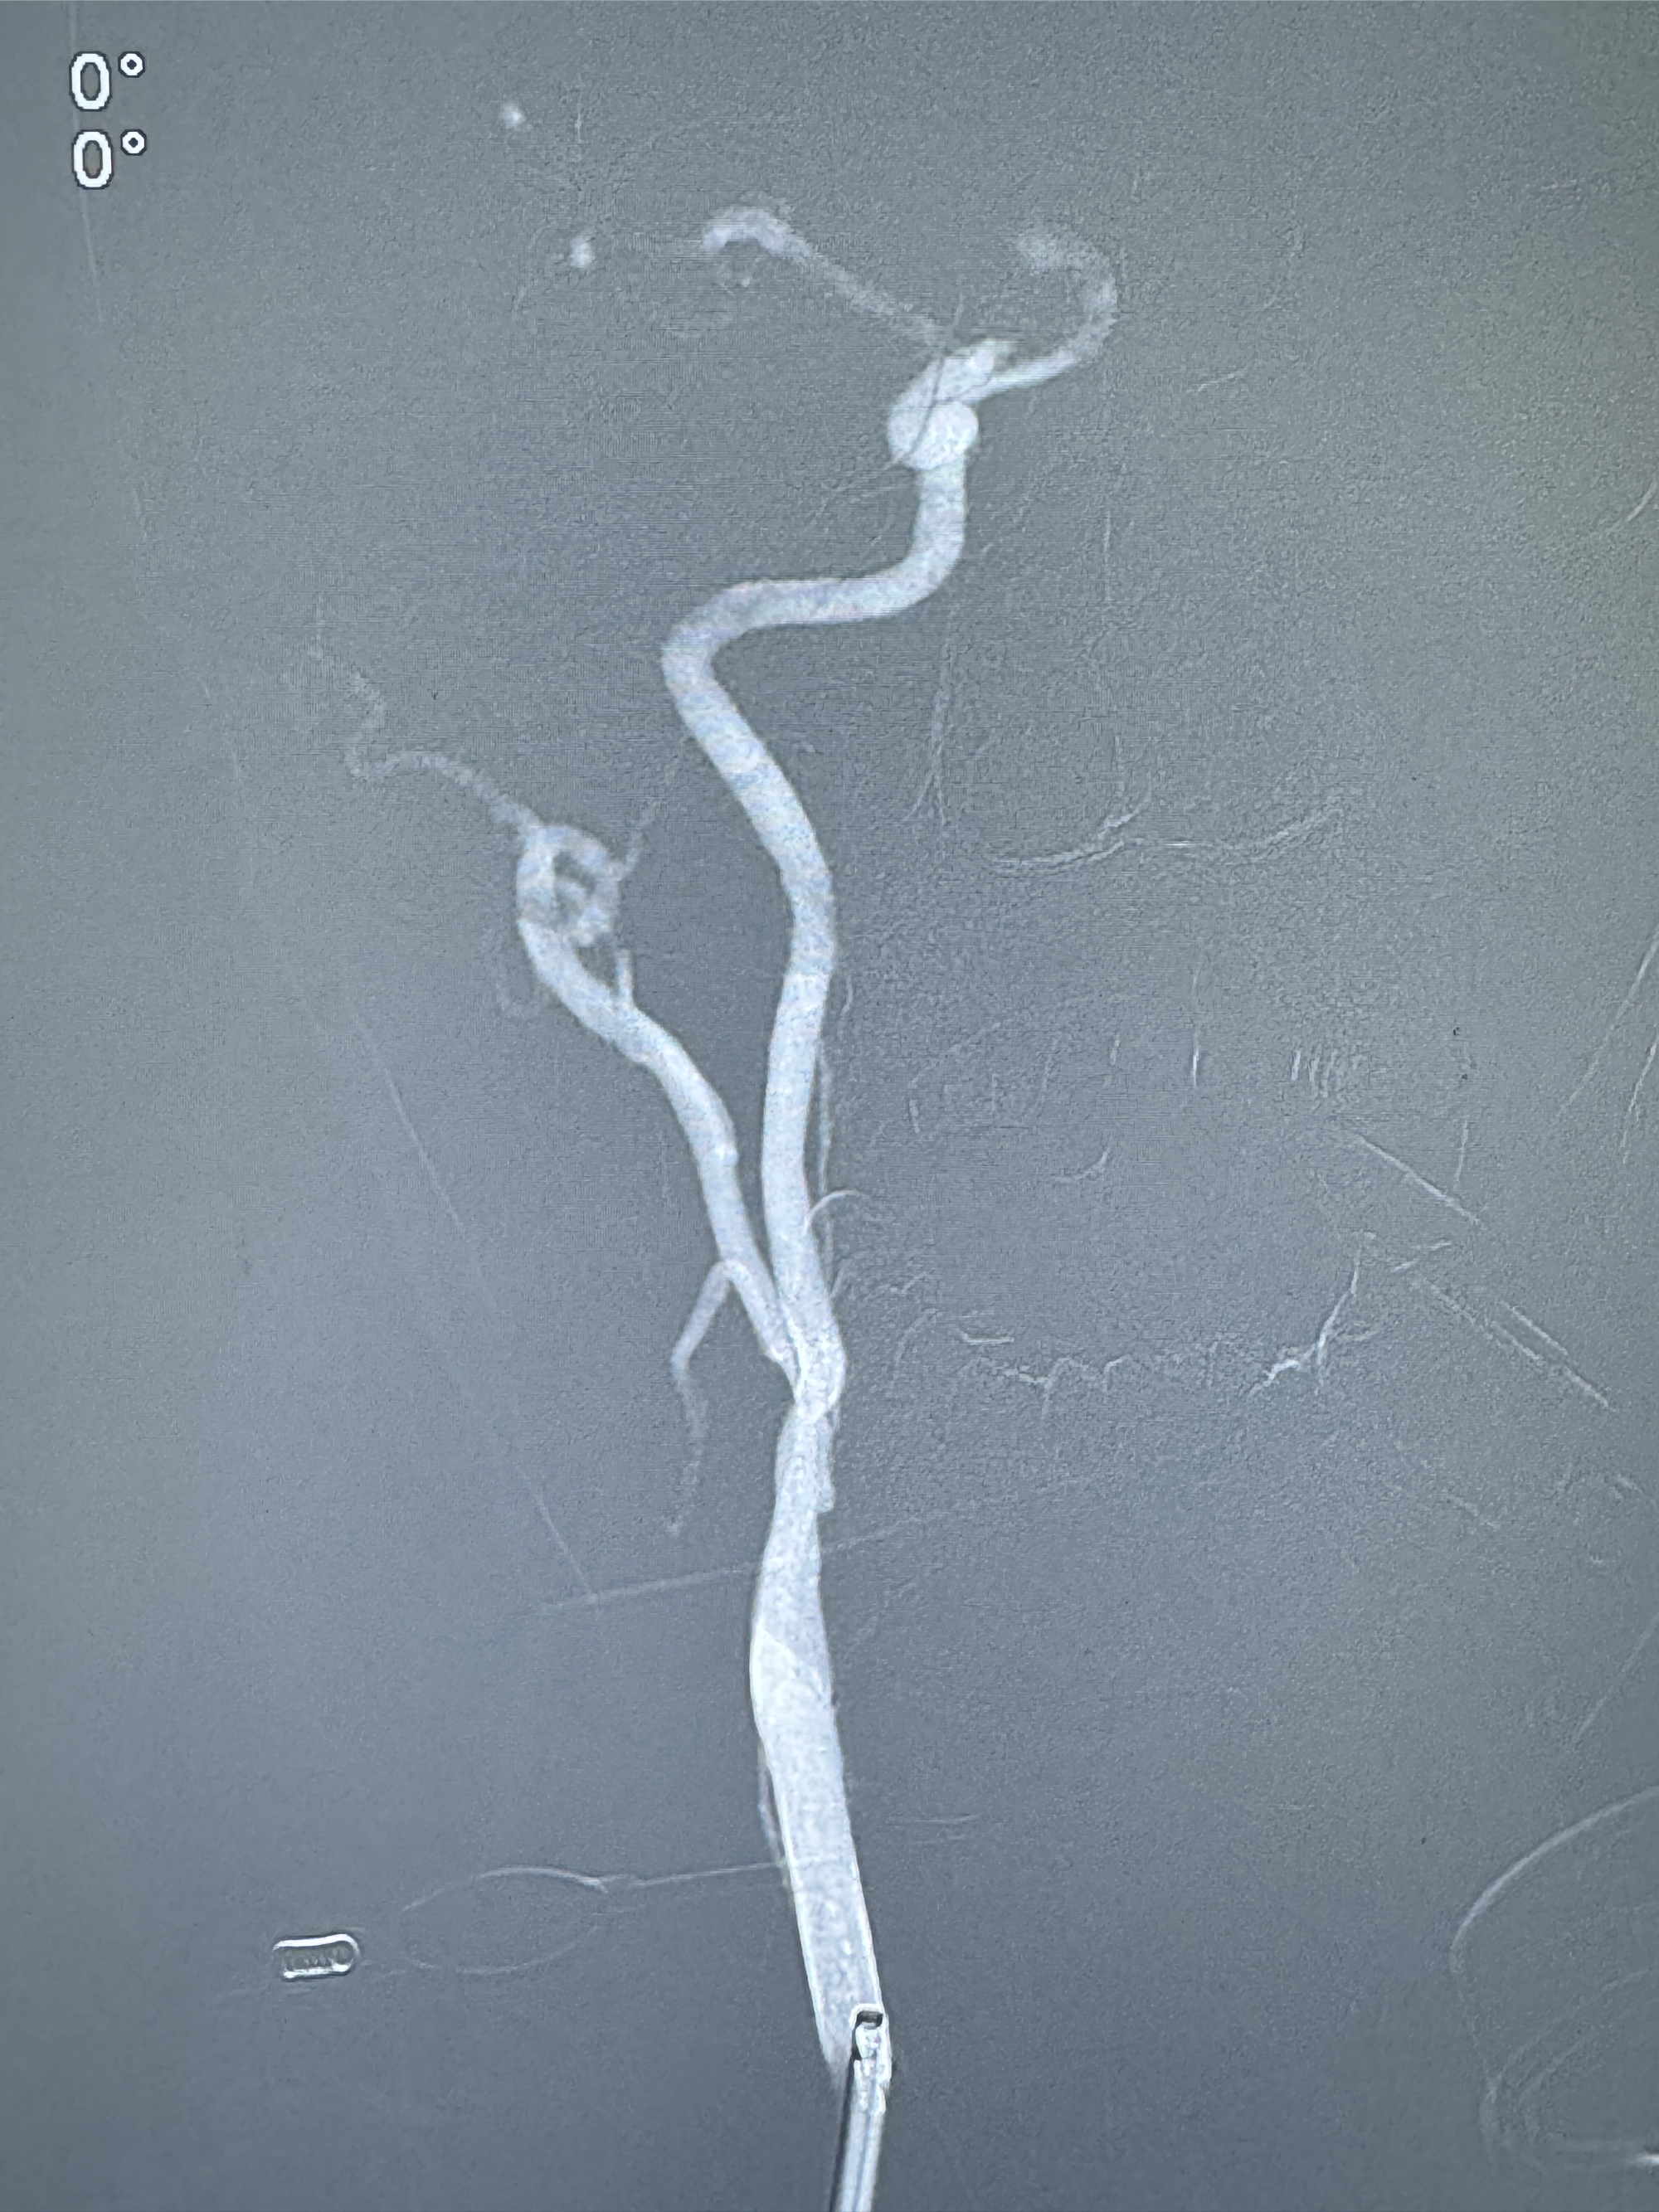

2024-01-08全麻下再行植入密网支架一枚

Tubridge 4.5-35mm

支架植入顺利,贴壁佳,支架内血流通畅,动脉瘤内血液滞留明显